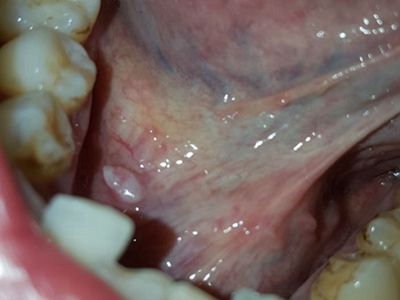

舌下腺囊肿舌头下面右侧有一个紫色包块图

舌下腺囊肿出现在口底舌系带一侧,表现为紫蓝色的隆起性包块,形态大致呈球形,界限清楚,质地柔软,囊肿增大后因破裂流出黏液。